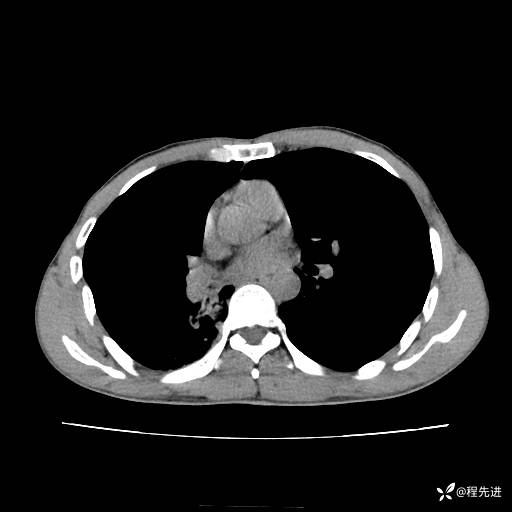

患者性别:男

患者年龄:49岁

主诉:咳嗽、胸痛1周

简要病史:1周前受凉感冒后开始出现咳嗽症状,阵发性连声咳,痰多,黄白痰,不易咳出,伴胸痛、气紧、胸闷,右侧为主,活动用力、呼吸时胸痛明显,曾在当地诊所贴敷膏药仍疼痛

体格检查:T:36.3 ℃ P:80 次/分 R:20 次/分 BP:120/88 mmHg,指脉氧饱和度97%,意识清晰,呼吸平稳,右侧第二、三肋骨压痛,可见膏药贴敷,皮肤无异常,双肺呼吸音粗,未闻及干湿性啰音。心率80次/分,节律整齐,无杂音。腹平软,全腹无压痛无反跳痛

临床诊断:社区获得性肺炎

CT平扫: